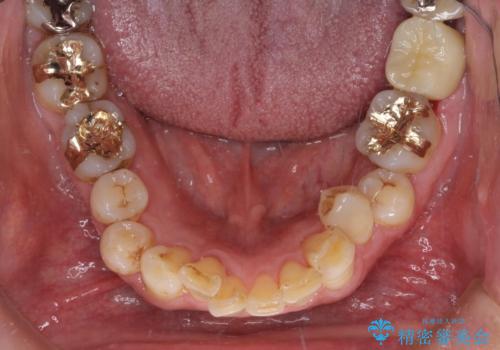

銀歯や虫歯を治したい ゴールドインレーによるむし歯治療

- 銀歯やインレーが外れたまま放置された奥歯の治療を希望して来院された患者様です。

咬合力が著しく強いため、欠損の多い歯はフルジルコニアクラウンへ、その他の虫歯はゴールドインレー(PGAインレー)にて修復することとしました。

来院時は全てセラミックでの治療を希望されていましたが、歯列や咬み合わせから咬合力による破損リスクが高いと判断されたため、ゴールドインレーを選択しました。